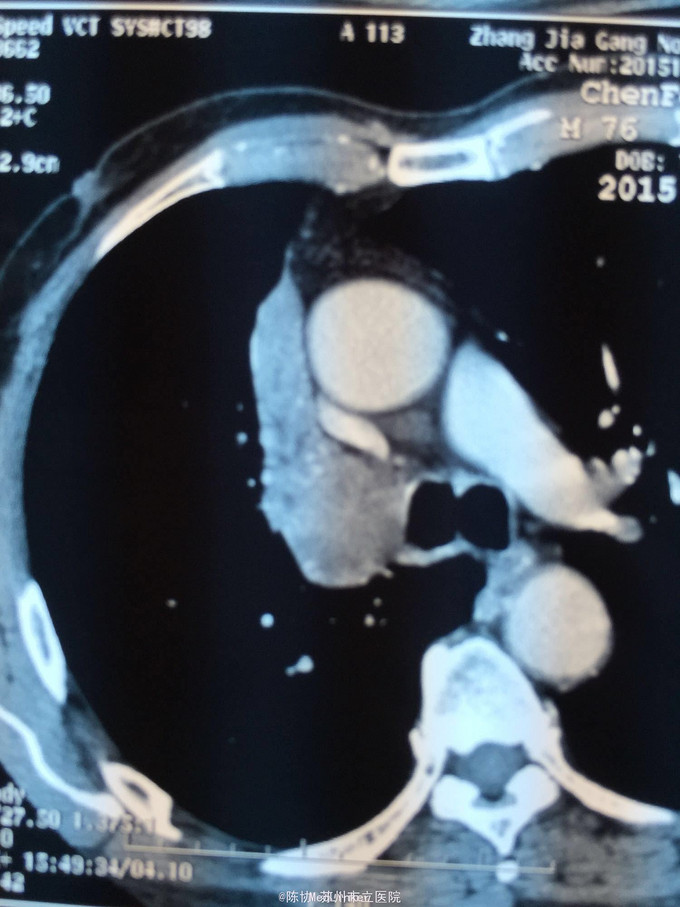

主诉:体检发现右上肺不张半月 77岁男,半月前体检发现右上肺不张,无不适。无消瘦,无咳血,无干咳。去年4月右上肺炎,抗生素治愈,当时CT未见肺肿块。入院支气管镜发现右上支气管开口组织增厚闭塞,开口近侧有隆起约3x3平方毫米,取活检5块病理示中度非典型增生。CT提示在右侧主支气管外侧有30x30平方毫米块影,压迫右上支气管开口处。三大常规和生化检查正常,肿瘤指标正常,TAP正常。

右侧中央型肺癌 重做支气管镜,精于定位找到病症组织,获得病理诊断来指导治疗。 胸外科医生不建议手术,理由是肿瘤位置靠近主支气管和气管,袖状切除不一定看干净。 请问正确的诊断,和比较合理的治疗方法是什么?求助大家思考评论